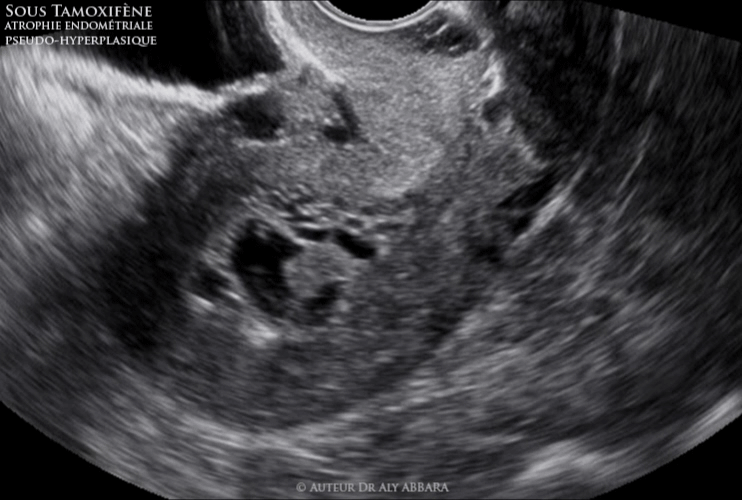

Atrophie endométriale pseudo-hyperplasique sous traitement par tamoxifène

Utérus : l'aspect échographique d'une atrophie endométriale pseudo-hyperplasique asymptomatique chez une patiente âgée de 81 ans traitée par tamoxifène depuis presque 5 ans.

Séquences vidéos et images échographiques montant un des aspects de l'endomètre sous traitement par tamoxifène, il s'agit d'une atrophie endométriale pseudo-hyperplasique.

L'endomètre sur ces images est de 19 mm d'épaisseur ; il est composé de très nombreuses vacuoles occupant la cavité utérine.